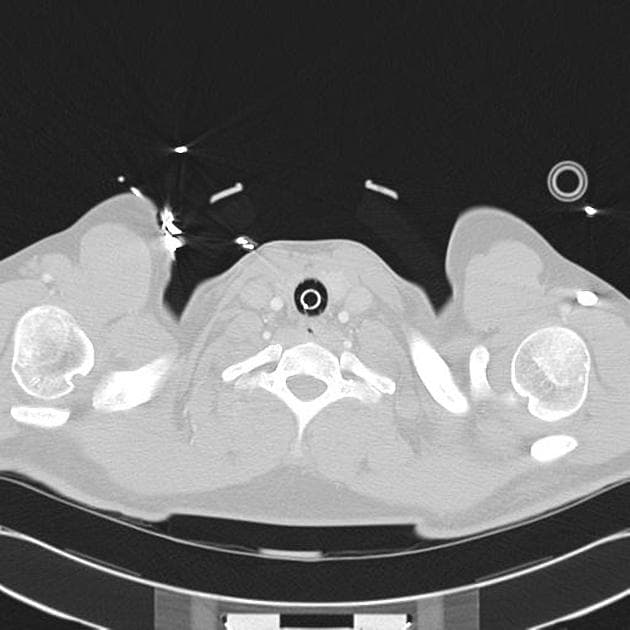

Phân tách động mạch chủ loại A theo Stanford trên CTPA

- Phân tách động mạch chủ ngực lên (ascending thoracic aortic dissection) kéo dài từ gốc động mạch chủ đến ít nhất là đoạn giữa động mạch chủ ngực.

- Tổn thương dạng sợi (stranding) quanh động mạch chủ lên và cung động mạch chủ, gợi ý nguy cơ vỡ sớm (early rupture).

- Động mạch vành phải (right coronary artery) có thể xuất phát từ lòng giả (false lumen).

- Động mạch vành trái (left coronary artery) xuất phát từ lòng thật (true lumen) với tình trạng vôi hóa nặng (heavy calcifications).

- Thời điểm tiêm thuốc cản quang (bolus timing) sớm đối với đánh giá thuyên tắc phổi (pulmonary embolus).

- Không thấy hình ảnh (no evidence of) thuyên tắc phổi lớn hoặc trung tâm.

Phân tách động mạch chủ loại A theo Stanford trên CTPA (Stanford type A aortic dissection on CTPA)